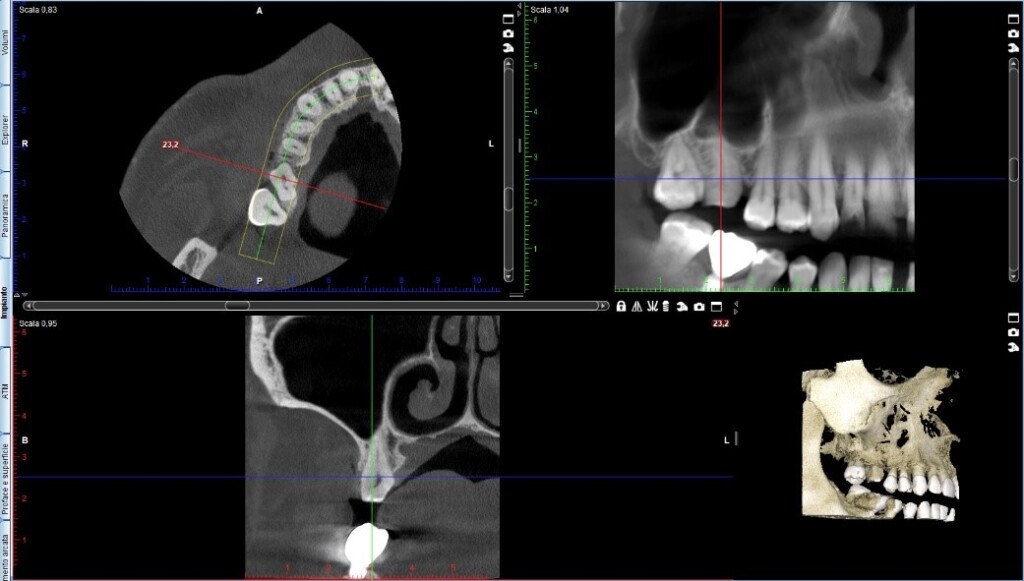

Sì perché, incredibilmente, il collega aveva fatto anche una tac. Guarda, ho fatto uno screenshot:

A parte che penso concordiamo tutti sul fatto che il dente non sia da togliere ma semplicemente da restaurare mantenendone la vitalità ma, ammesso anche che uno volesse proprio toglierlo sono sicuro che il consulente maxillofacciale del collega non avrebbe avuto la minima difficoltà nel posizionare un impianto in seguito.